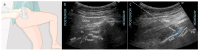

The incidence of hip fractures has continued to increase as life expectancy increases. Hip fracture is one of the leading causes of increased morbidity and mortality in the geriatric population. Early surgical treatment (<48 h) is often recommended to reduce morbidity/mortality. In addition, adequate pain management is crucial to optimize functional recovery and early mobilization. Pain management often consists of multimodal therapy which includes non-opioids, opioids, and regional anesthesia techniques. In this review, we describe the anatomical innervation of the hip joint and summarize the commonly used peripheral nerve blocks to provide pain relief for hip fractures. We also outline literature evidence that shows each block's efficacy in providing adequate pain relief. The recent discovery of a nerve block that may provide adequate sensory blockade of the posterior capsule of the hip is also described. Finally, we report a surgeon's perspective on nerve blocks for hip fractures.

Keywords: fascia iliaca block; lateral femoral cutaneous nerve; pericapsular nerve group (PENG) block.